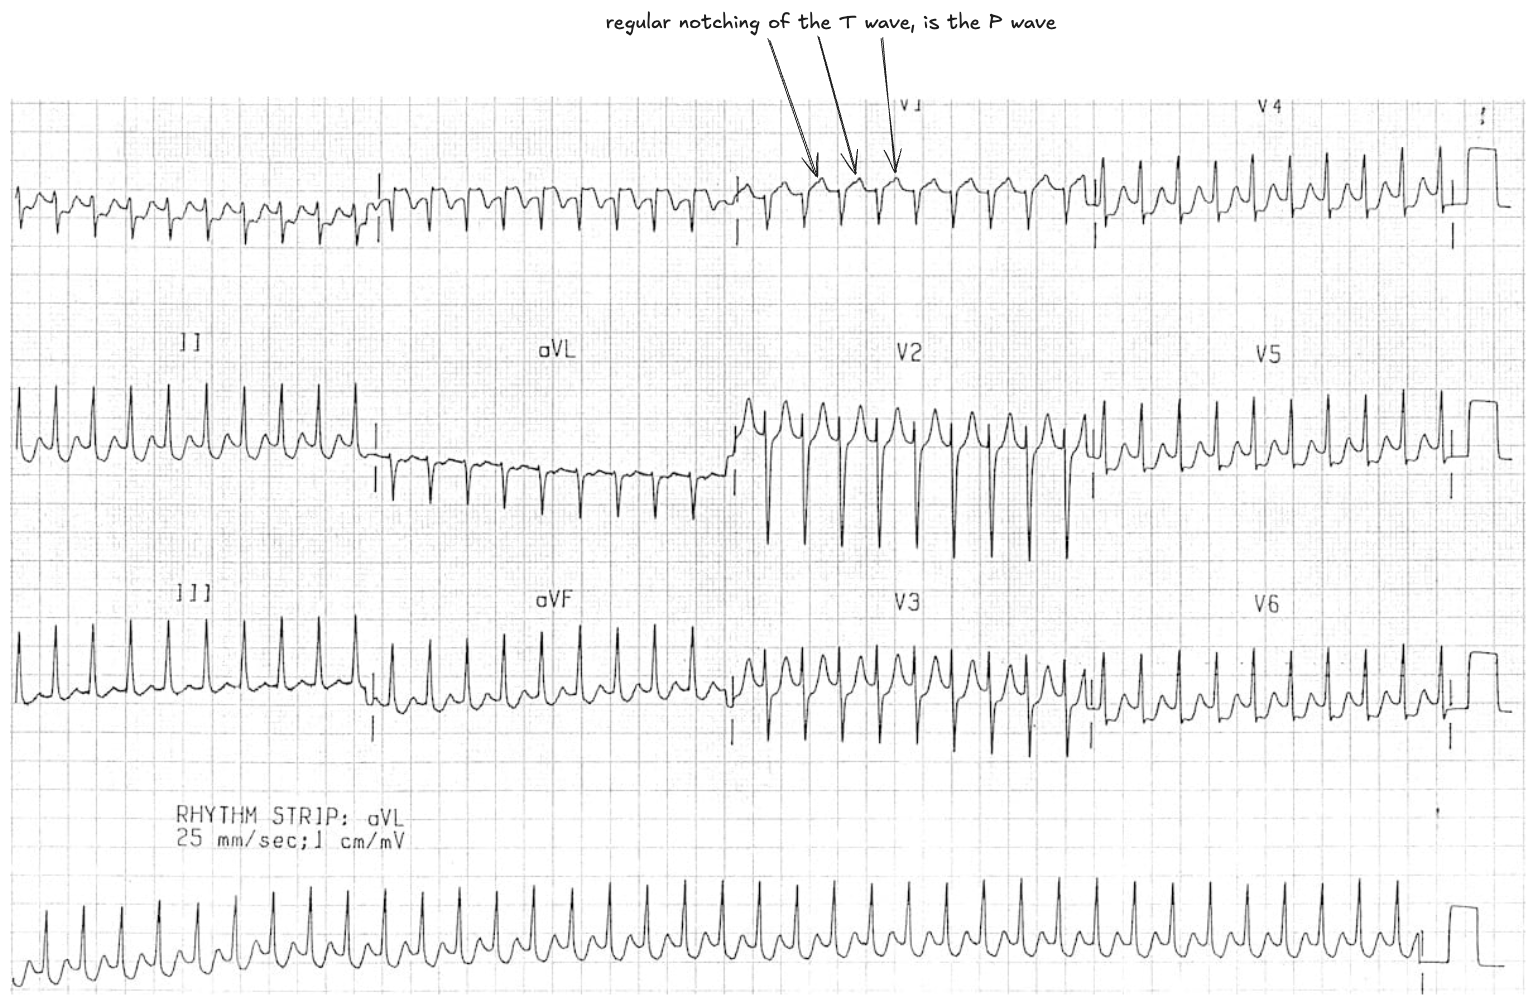

- Regular broad complex tachycardia ~280 bpm

- The patient is 5 year old by and VT is very unlikely in this demographic

- Rhythm resolved with vagal manoeuvres (despite it probably not being safe to do this)